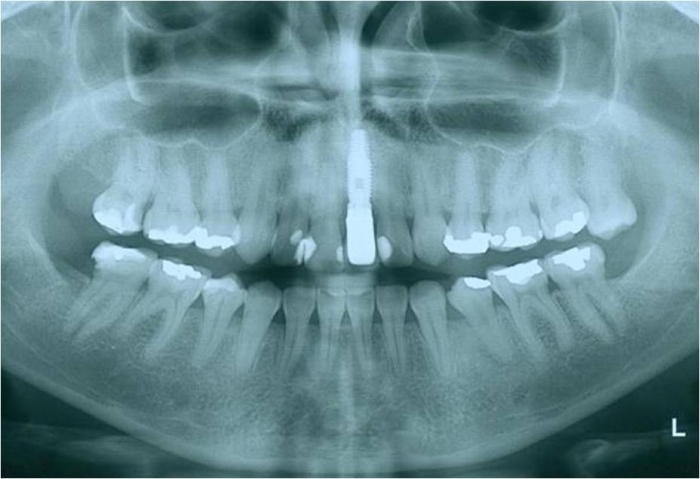

Dente 21 com fratura

Raio X inicial do dente 21 fraturado